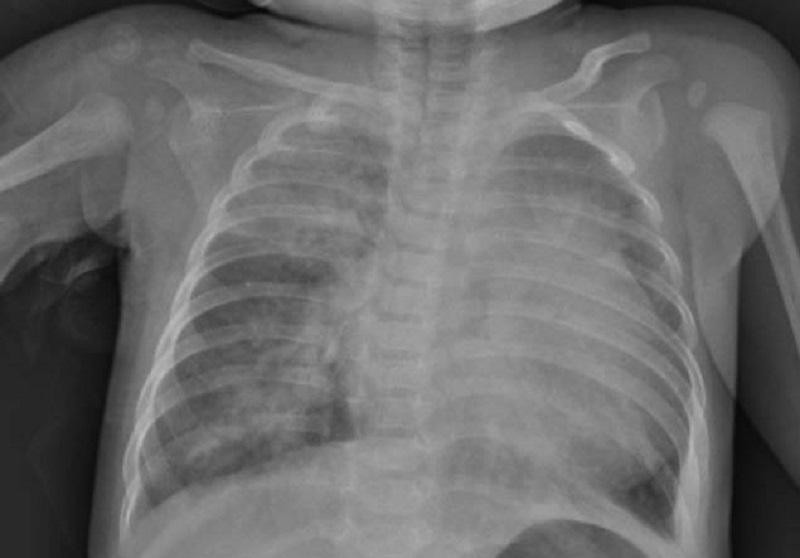

| X-quang ngực cho thấy hình ảnh tổn thương thâm nhiễm phổi nặng lan tỏa 2 phế trường, bóng tim to (ảnh: BVCC) |

Tại thời điểm nhập viện, chỉ số oxy máu của bệnh nhi giảm sâu (còn 78%), nhịp tim nhanh (168 lần/phút). Kết quả xét nghiệm khẳng định, trẻ bị nhiễm SARS-CoV-2. Kết quả thăm khám, chẩn đoán hình ảnh cho thấy, bé bị bệnh tim bẩm sinh (thông liên nhĩ, còn ống động mạch). Cùng lúc bị 2 chứng bệnh nguy hiểm, tiên lượng điều trị cho bệnh nhi vô cùng khó khăn.

Hình ảnh Xquang phổi cho thấy, bé bị tổn thương phổi nặng lan tỏa 2 bên, hội chứng suy hô hấp cấp tiến triển (ARDS), suy tim. Xét nghiệm máu cho thấy có biểu hiện phản ứng viêm tăng mạnh… Sau hội chẩn, các bác sĩ đã quyết định mở khí quản cho trẻ thở máy và truyền thêm kháng thể miễn dịch, điều trị các thuốc hỗ trợ tim, tăng sức co bóp cơ tim.